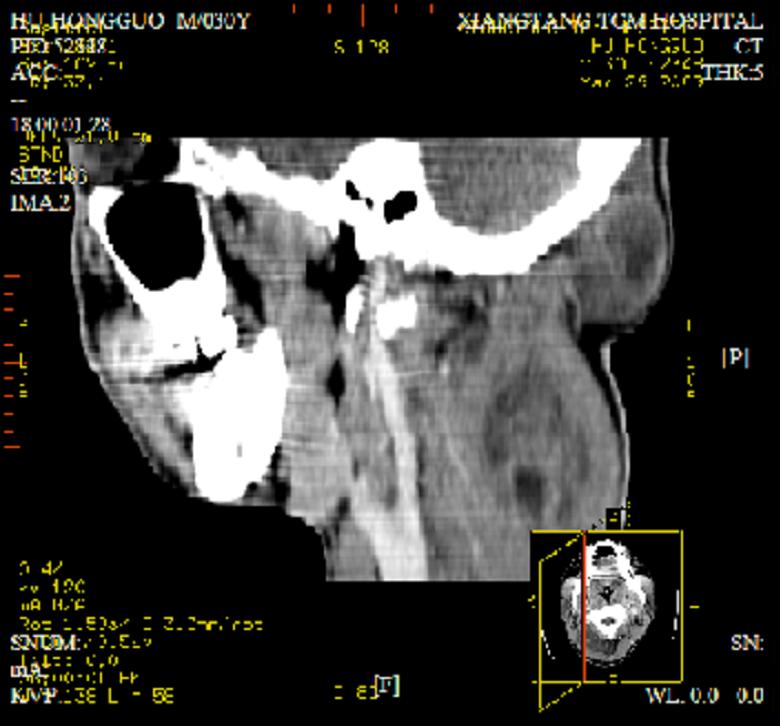

标题: CT19102:颈部肿块

男30y发现肿块3年

多处囊实性肿块,形态欠规则有一定形态,内见点状钙化,以囊变为主,增强后轻度强化,首先考虑神经源性肿瘤如鞘瘤,不除外脉管源性肿瘤如淋巴管瘤(见缝钻及囊性区域太多,如果合并感染完全可以这个影像表现),和海绵状血管瘤,但是血管瘤不太支持因为强化特征和病灶形态不典型.

右侧椎前间隙后部肌间、皮下囊性为主病变,可见分隔和点状钙化,分隔和壁呈轻度环形强化,大部分无强化。形态不规则,有钻缝特点。考虑1 淋巴管瘤合并感染2 血管平滑肌脂肪瘤3 表皮样囊肿4 不除外海绵状血管瘤。

病灶沿皮下及肌间隙爬行,病灶内有钙化灶,病灶有强化。病史3年,病人应该没什么症状。考虑纤维血管瘤可能性大。